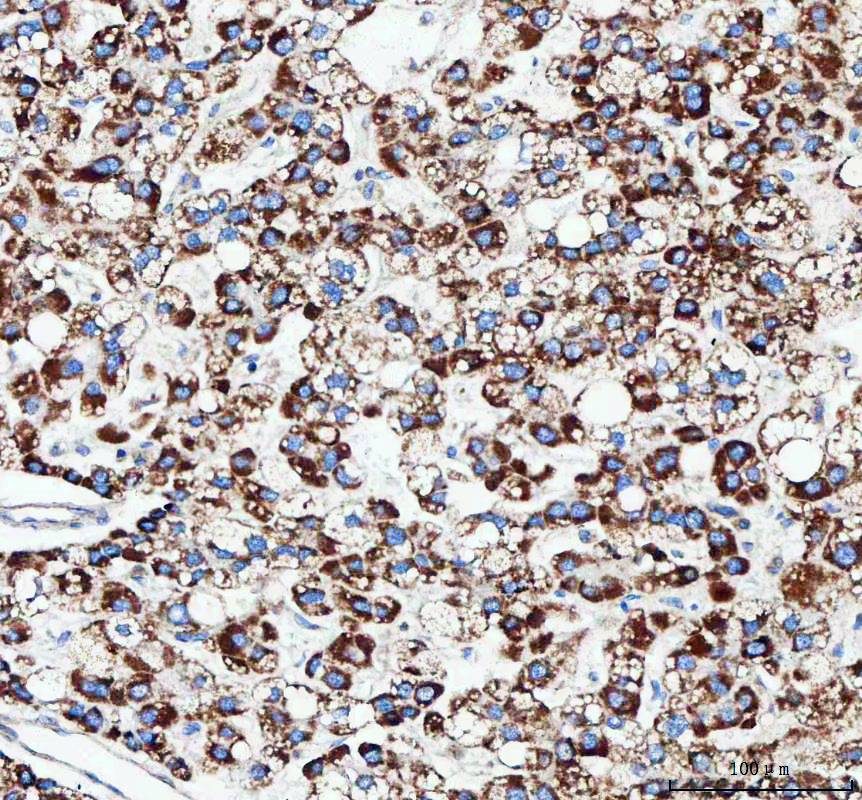

IHC analysis of TFAM using anti-TFAM antibody (BA2827) .

TFAM was detected in a paraffin-embedded section of human intestinal diffuse large B-cell lymphoma tissue. The tissue section was incubated with rabbit anti-TFAM Antibody (BA2827) at a dilution of 1:200 and developed using HRP Conjugated Rabbit IgG Super Vision Assay Kit (Catalog # SV0002) with DAB (Catalog # AR1027) as the chromogen.